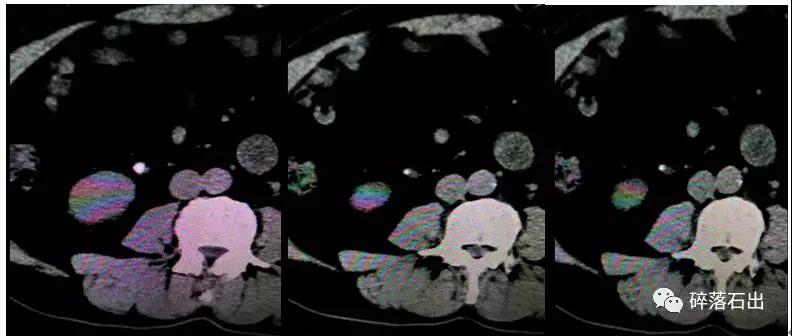

圖1圖2腎積水明顯,腎盂輸尿管中度擴(kuò)張;圖3輸尿管管壁不規(guī)則;圖4圖5圖6提示輸尿管結(jié)石切面輸尿管管壁厚度異常。

上面系列圖可見(jiàn):結(jié)石顆粒并不大,但影響的積水卻不輕,也能間接提示周圍有息肉包裹。另外,經(jīng)驗(yàn)告訴我們,當(dāng)碎石治療過(guò)程中發(fā)現(xiàn)結(jié)石破碎不理想時(shí),及時(shí)改變體位更換沖擊波方向,會(huì)產(chǎn)生更好的效果,這可能與結(jié)石表面應(yīng)力有關(guān)。若經(jīng)過(guò)2次碎石療效不佳,在排除碎石機(jī)定位系統(tǒng)無(wú)誤外,建議改行其他治療方法。

圖4 圖5 圖6